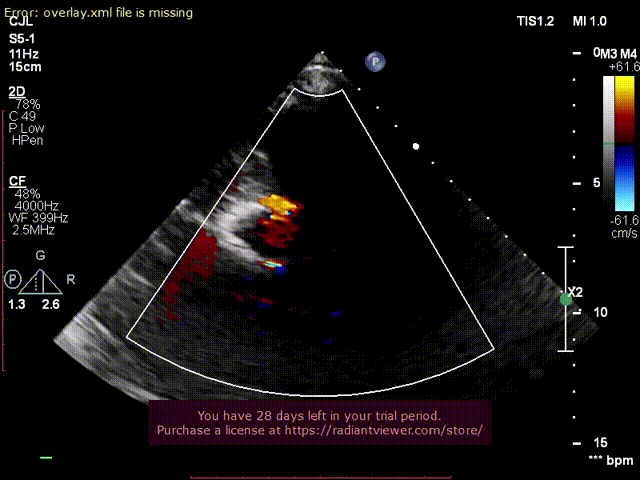

超声术后评估:

超声显示假体瓣膜形态良好,工作正常,少量瓣周漏。

超声显示假体瓣膜形态良好,工作正常,微量瓣周漏。